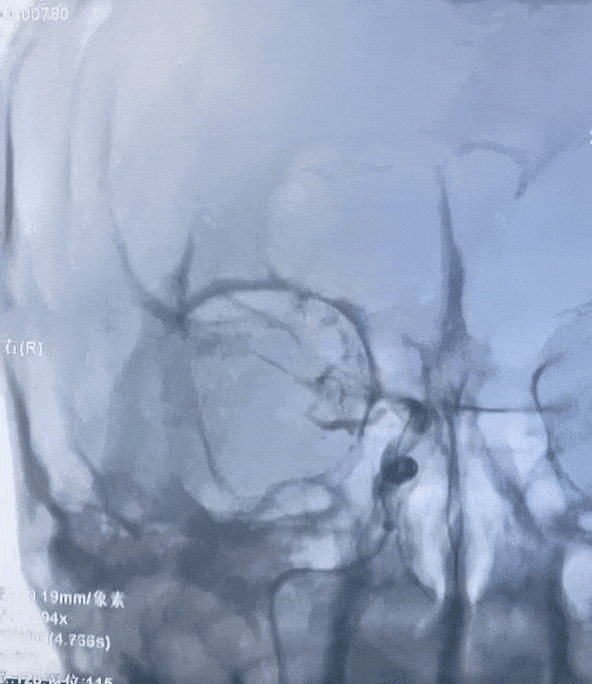

右侧前循环造影,颈内动脉闭塞。

动脉长鞘怎么置入有励可说|Locaste 088励楷长鞘在右侧颈内动脉闭塞并夹层术中的应用_https://www.jmylbn.com_新闻资讯_第6张